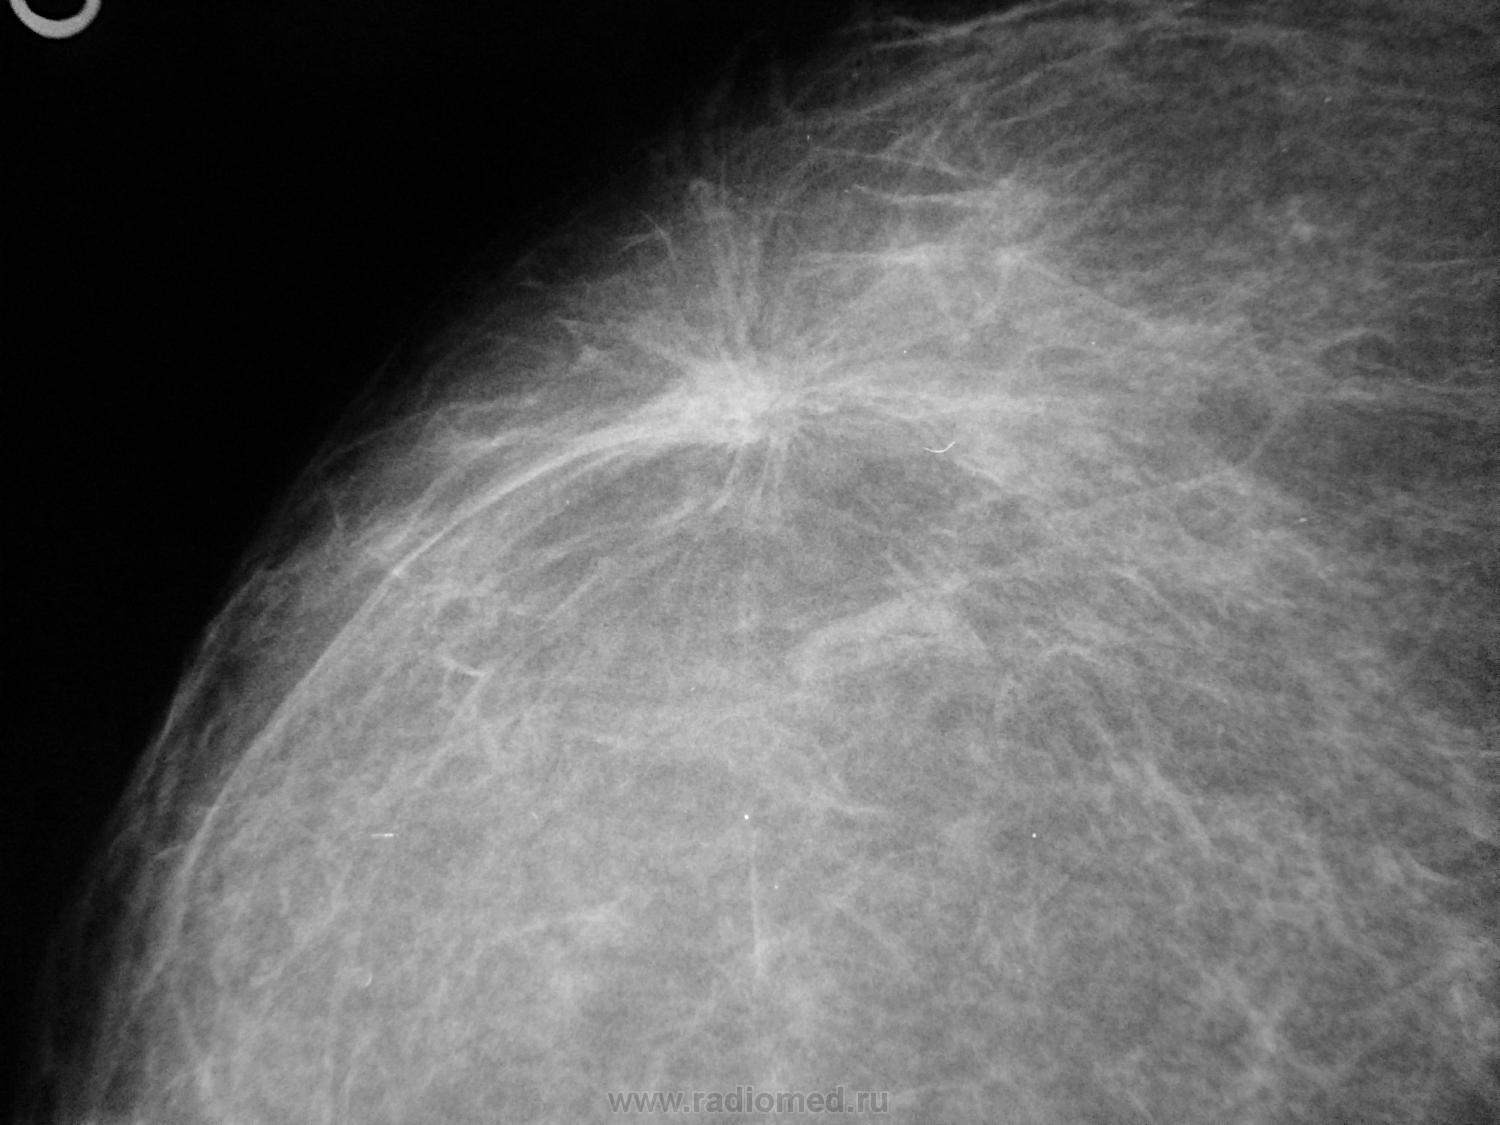

Опухоль на снимке маммографии

Злокачественные опухоли молочных желез

Маммография и ее роль в диагностике фиброаденомы молочной железы

Маммография - это рентгенологическое исследование молочных желез. Оно позволяет выявить различные изменения в тканях, включая фиброаденому. На маммограммах можно увидеть структурные особенности опухоли и отследить ее динамику во времени.